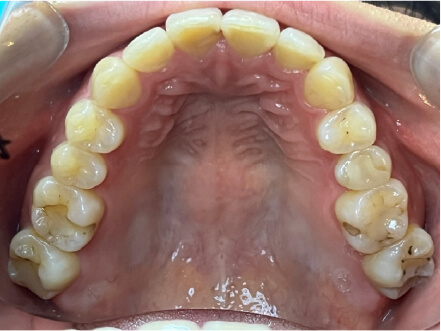

叢生の症例

19歳

女性

上の前歯が出っ歯、下の前歯がガタガタ

カウンセリング・診断結果

抜歯承諾、IPR承諾、アタッチメント承諾、ミニインプラント承諾、アレルギー有・叢生(凸凹)

治療内容・方法

全顎アライナー矯正 抜歯予定だったが抜歯リスク高いため抜歯なしでIPR量を増やす

術後の経過・現在の様子

クリアライナー

痛み・歯根吸収・歯肉退縮・虫歯・後戻り

費用・治療期間

880,000円、1年5ヶ月